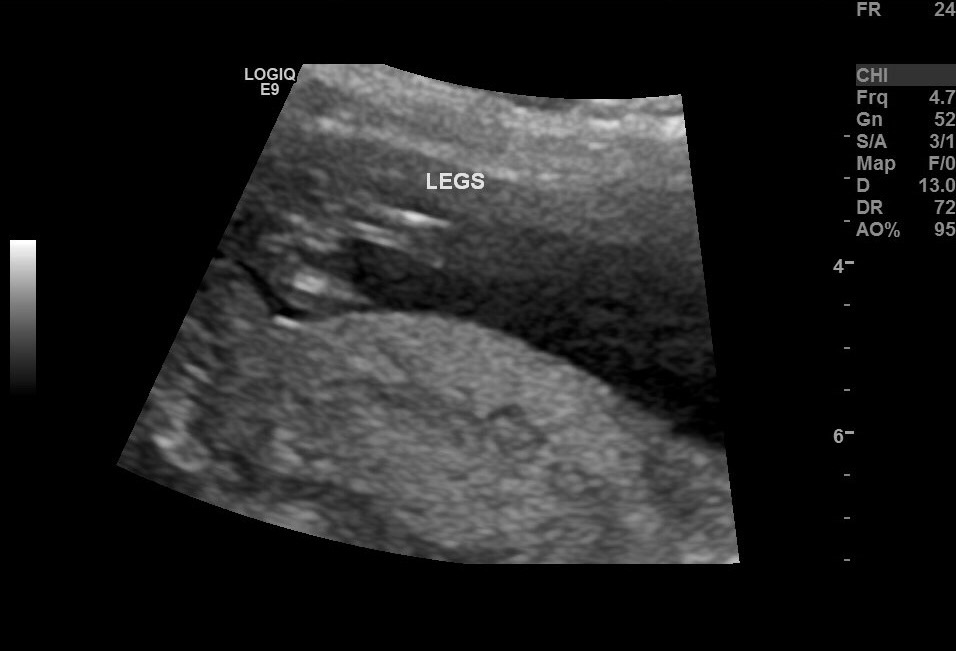

Hey everyone.. I had a scan yesterday at exactly 13 weeks & I think I got some good pictures but I just can't tell if there is any significant angle so I'd love your help :)

I adjusted the pic a bit so that the babies back is flatter & there is a rise but it's definitely not more than 30 degrees. Probably about 20 degrees. I'm also unsure how accurate the potty shot is because I didn't ask the sonographer to take a pic, that's just the one she took of the legs :)